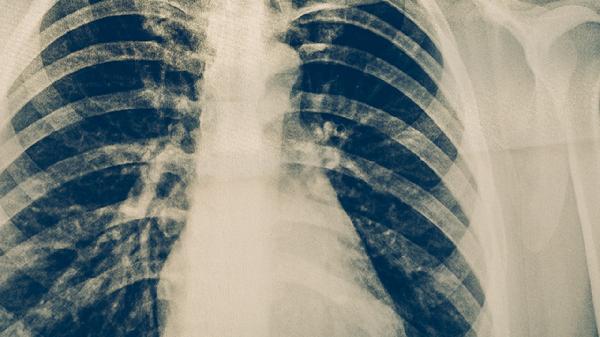

治愈标准需经影像学确认病灶钙化或纤维化,此时结核分枝杆菌处于休眠状态,不再通过飞沫传播。治疗结束后需复查胸部CT,若显示陈旧性病变则无传染风险。

治愈后保持均衡饮食有助于肺部修复,每日摄入足量优质蛋白如鱼肉、豆制品,补充维生素A、D促进黏膜再生。适度有氧运动如八段锦可改善肺功能,但需避免粉尘环境。定期随访监测5年内复发率低于3%,接触者出现可疑症状时应及时进行胸部X线检查。居住环境保持日均通风2小时以上,被褥定期阳光暴晒杀菌。